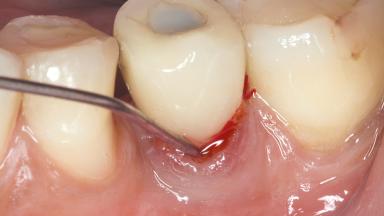

Mauricio Araujo and Flauvia Matarazzo present this straightforward clinical case, demonstrating the potential effect of implant placement depth on the resolution of peri-implant treatment. A 42-year-old systemically healthy female patient, a non-smoker with no history of periodontitis, was treated at the Dental Clinic at the State University of Maringá, Brazil between 2008 and 2009, when she received five implants restored with single crowns at sites 14, 26, 27, 36, and 46. After delivery of the implant-supported prosthetic restorations, the patient was enrolled in the supportive peri-implant therapy (SPiT) maintenance program at the same university.